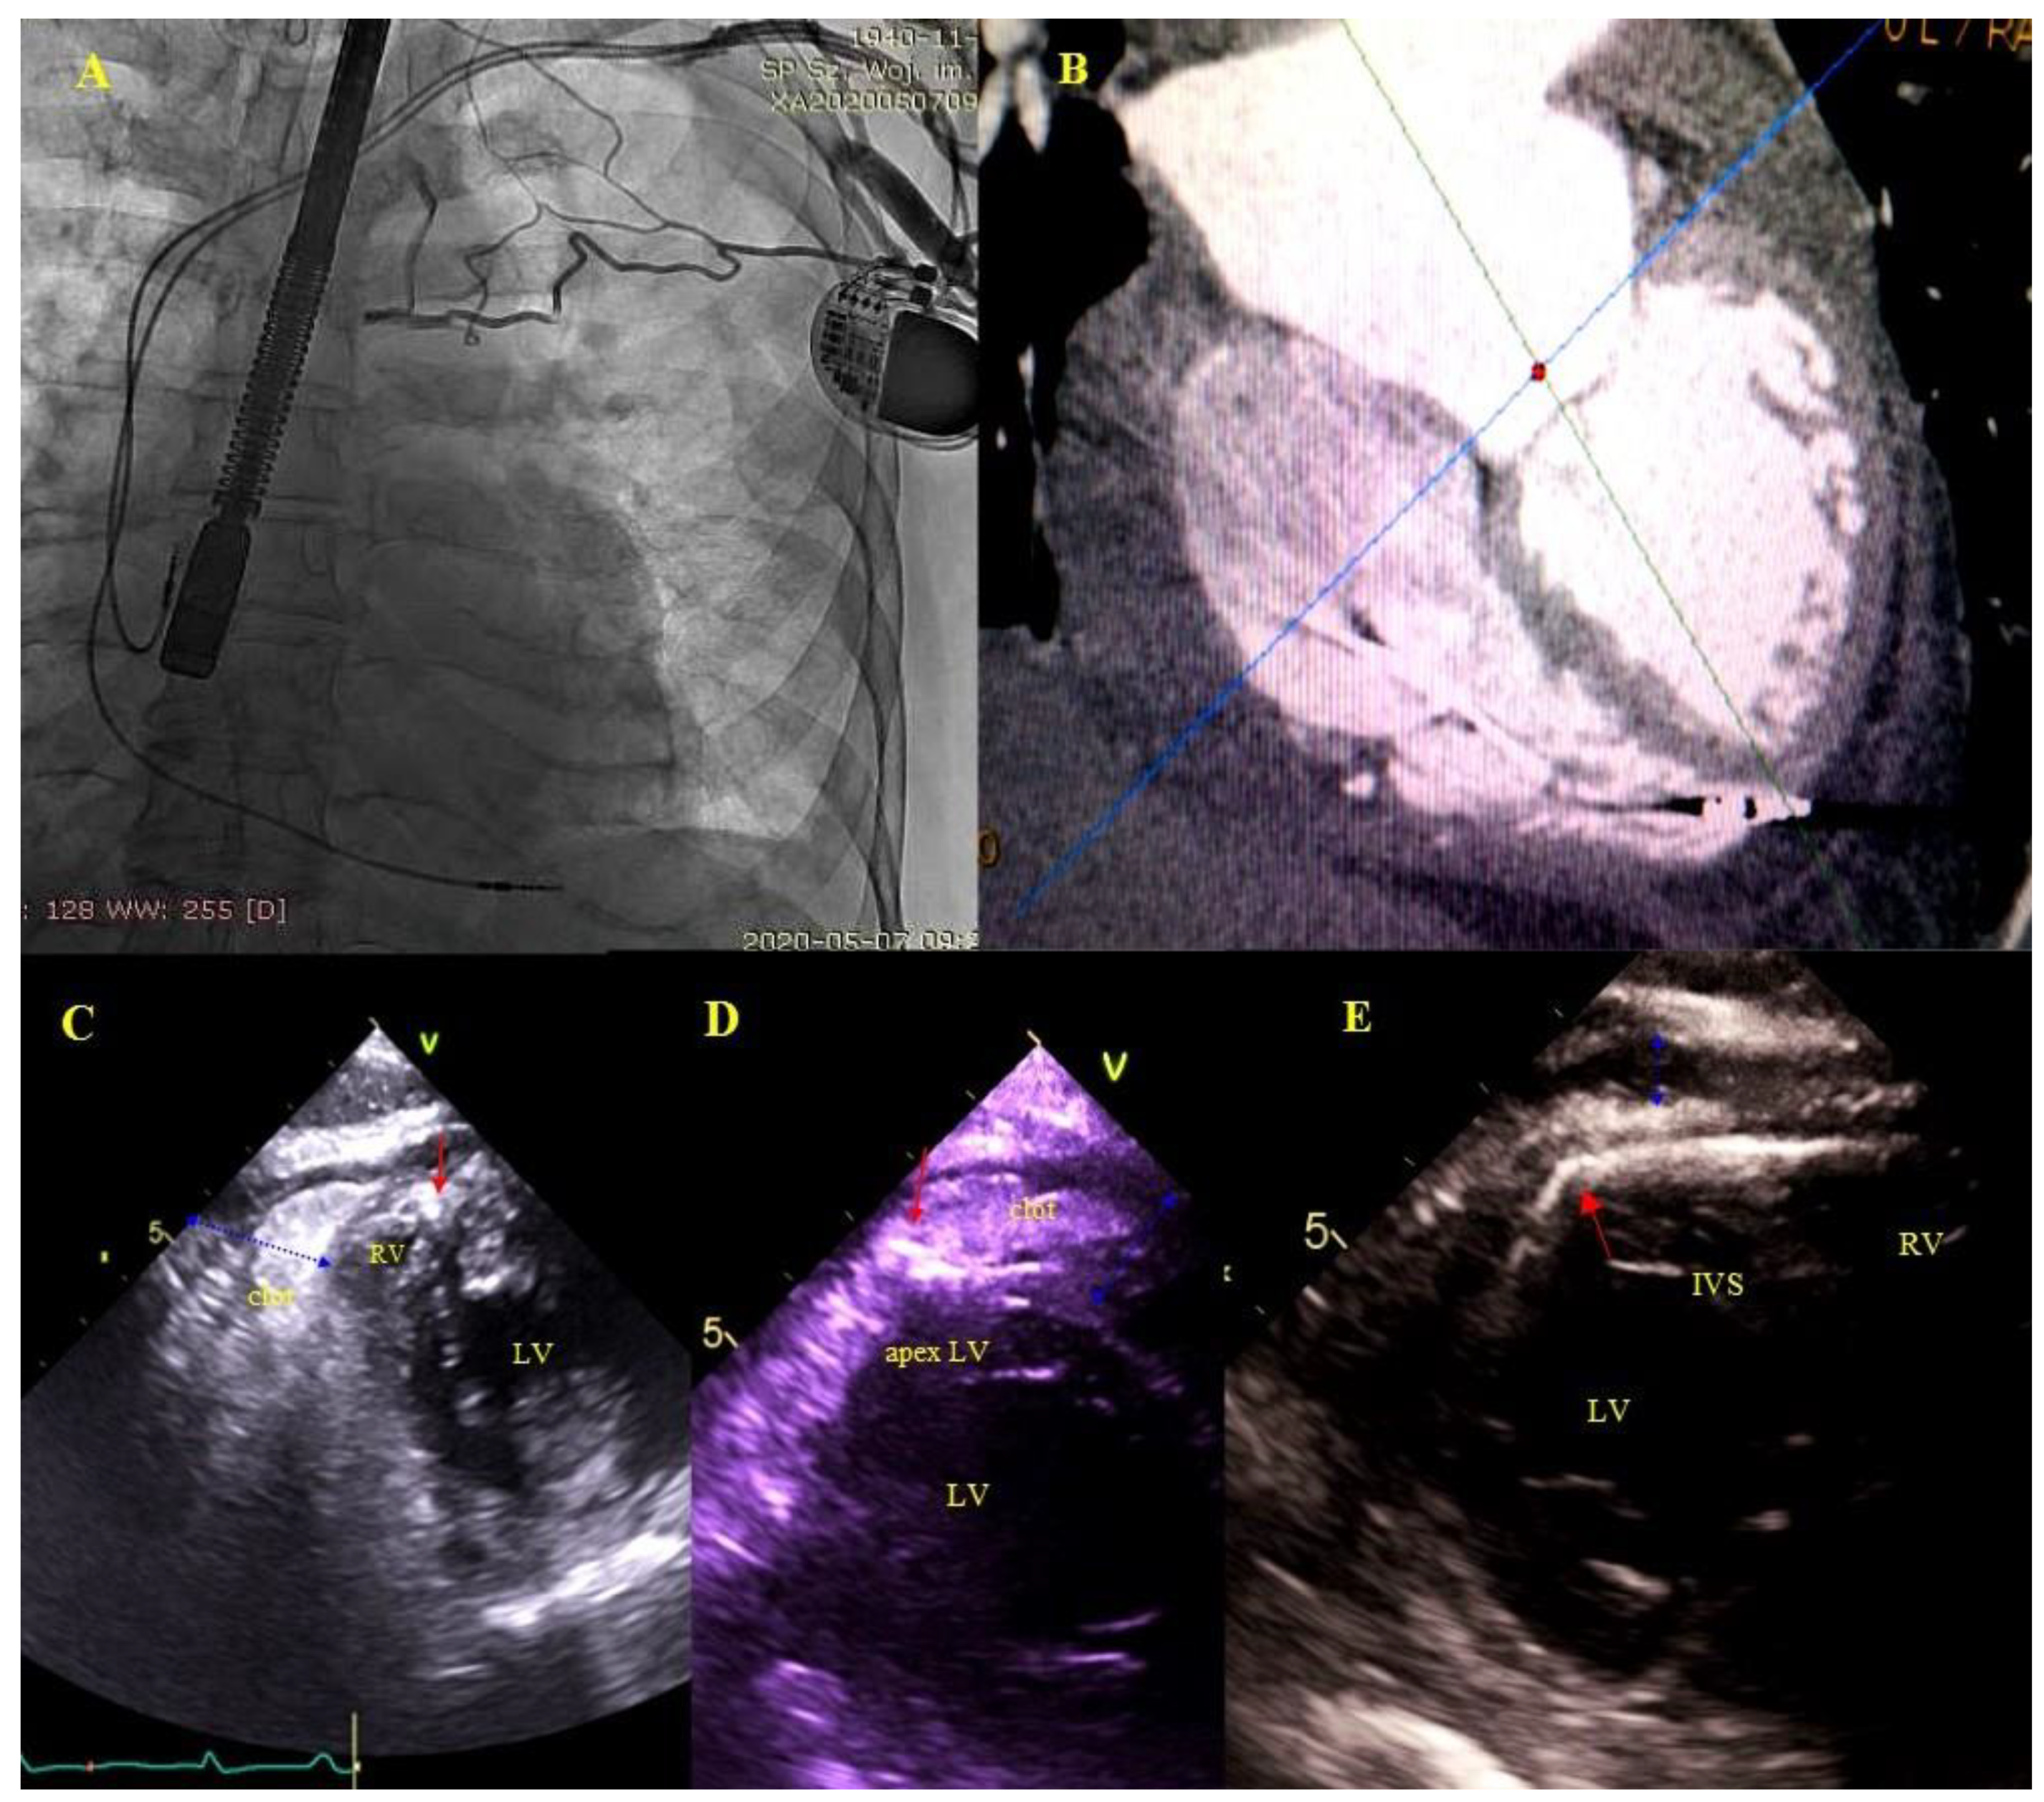

2.5. Echocardiographic Findings Associated with Endocardial Leads: Definition and Classification According to the Anatomy and Characteristic Features

- Factors that have no effect on the procedure course and chances of long-term survival: AMEL (clots, vegetation-like masses) had no influence on chances of long-term survival in our analysis.

- Perforation, penetration—as was the case of lead loops, perforation/penetration was the main or accompanying indication for lead extraction (most of them were “dry” and caused lead dysfunction or, less frequently, it was an incidental finding or the cause of fluid accumulation in the epicardial space). All perforating/penetrating leads were replaced, thus eliminating their influence on survival and future quality of life. Similar to lead loops, perforations in univariate and multivariate Cox analysis of Model 1 were significantly related to better survival odds.